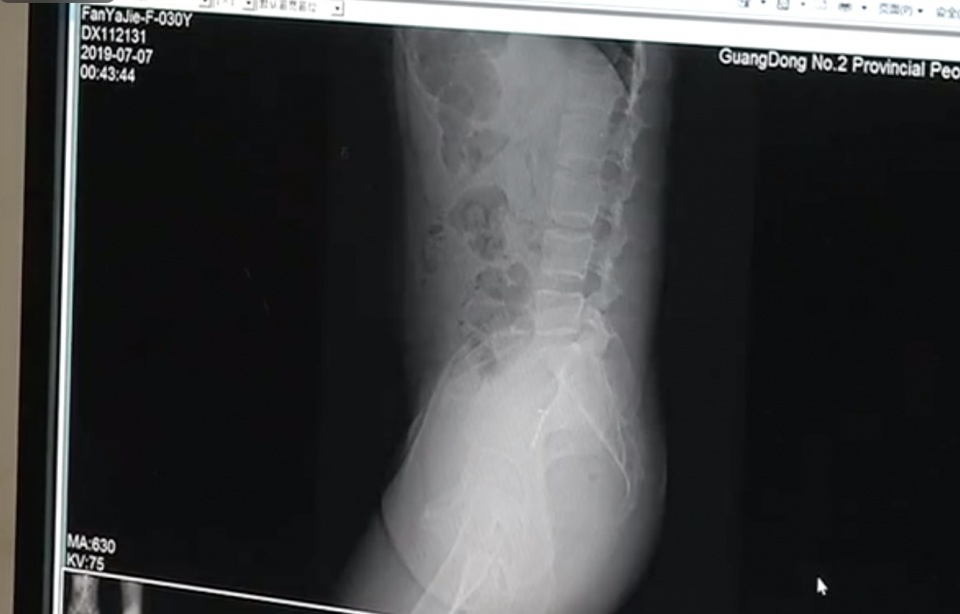

考虑到邢女士受伤的部位比较特殊,医生同时邀请了妇科、泌尿外科、内镜中心一起会诊,当时她截石位6点钟方向自皮肤至肛管大片撕裂,长度大概4厘米。

医生:基本排除泌尿系和生殖系统的问题,后面的治疗基本明确是直肠肛管的损伤,大概在当晚两点钟左右给患者做了一个全麻手术,手术内容是给患者做直肠肛管的清创处理。